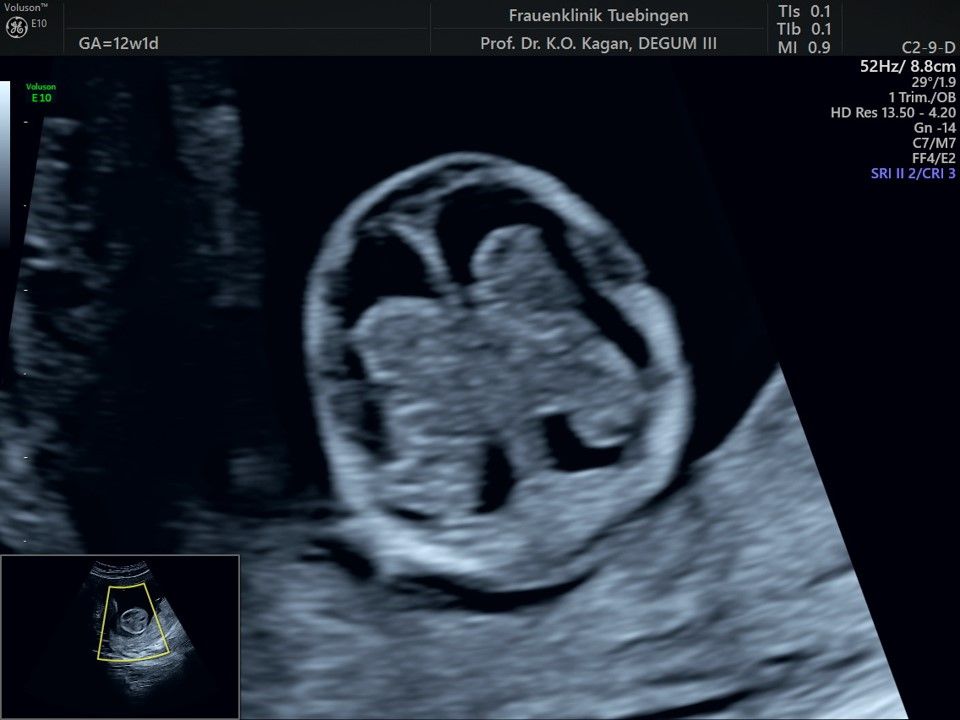

Im Rahmen des Ersttrimester-Screenings untersuchen wir die Organe des Feten mittels Ultraschall. Dabei machen wir auch gerne ein Bild für Sie.

Obwohl der Fet zu diesem Zeitpunkt erst zwischen 5 und 8cm groß ist, lassen sich bereits etwa die Hälfte aller schwerwiegenden Fehlbildungen erkennen bzw. ausschließen. Sollten wir eine Auffälligkeit sehen, werden wir mit Ihnen den Befund und das weitere Vorgehen ausführlich besprechen.

Fetale Anatomie